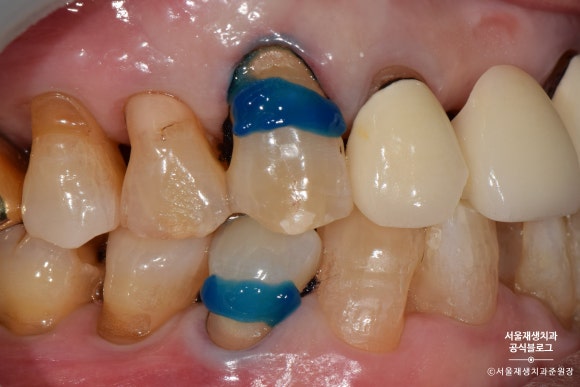

레진으로 치경부마모증 치료하기

레진은 글라스아이오노머에 비해

치료 과정이 복잡하고 술자의 손기술에 결과가 많이 좌우됩니다.

서울재생치과에서는 서울대 치과보존과 전문의인 전준희 원장이

대학병원의 프로토콜을 준수하며 직접 진료합니다.

레진이 접착될 부위를 깨끗하게 소독하고

약제를 도포합니다.

레진을 치아에 접착시키는 약제를 도포합니다.

레진을 한 겹, 한 겹 정성껏 쌓아올립니다.

이때, 침이나 물 한방울도 튀지 않도록 조심!

들뜬 자리가 없도록 꼼꼼하게 레진을 다듬어줍니다.

사진상으로는 모두 나오지 않지만,

반질반질하고 심미적인 결과를 위해서

여러번의 마무리 과정을 거치게 됩니다.

짠!

완성되었습니다.